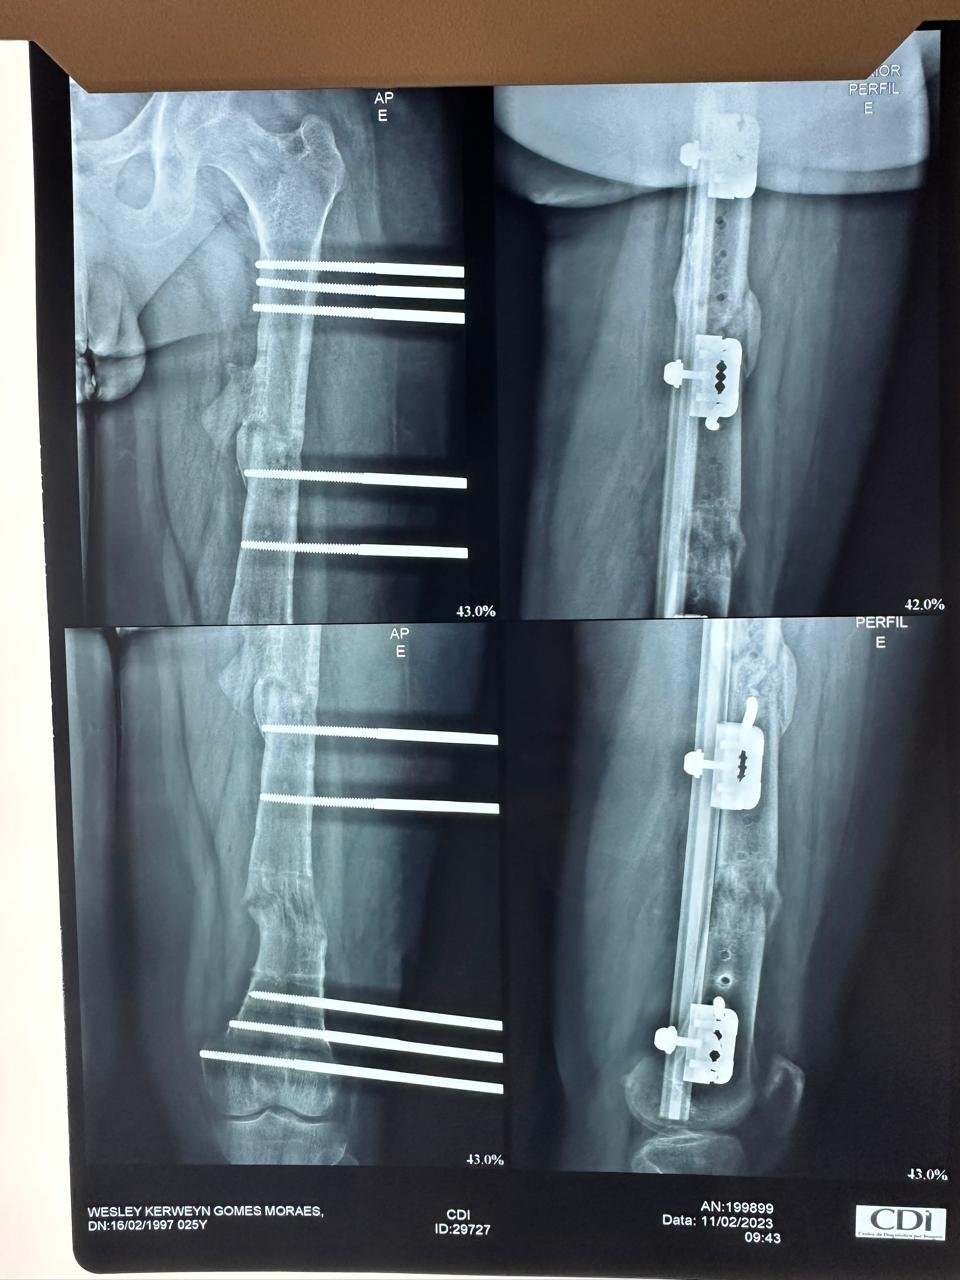

A cirurgia de alongamento ósseo para ganho de estatura é uma das áreas de maior expertise do Dr. Alano. Utilizando as técnicas mais inovadoras, como os sistemas telescopados PRECICE e FITBONE, além da abordagem combinada de alongamento sobre haste (LON), o procedimento proporciona crescimento gradual, seguro e esteticamente satisfatório. Esta é uma solução cada vez mais procurada por adultos com baixa estatura, que buscam não apenas ganho físico, mas também autoestima e autoconfiança.

Tratamento de Pseudoartroses: Atuação especializada na consolidação de fraturas que não cicatrizaram adequadamente, com técnicas avançadas de reconstrução óssea.